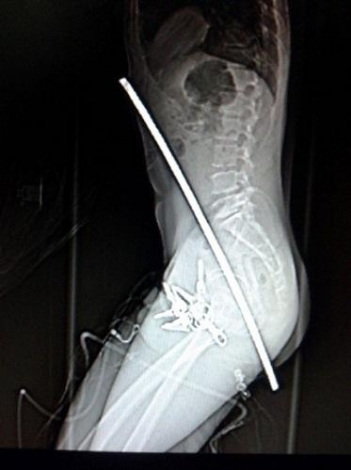

8241488971580176030.jpg

中國合肥的一位建筑工人從腳手架上摔下,導致一根鋼筋刺穿他的身體。